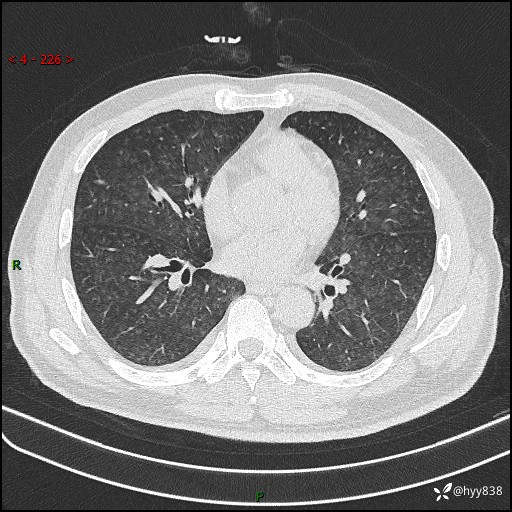

辅助检查:CT

胸部HRCT